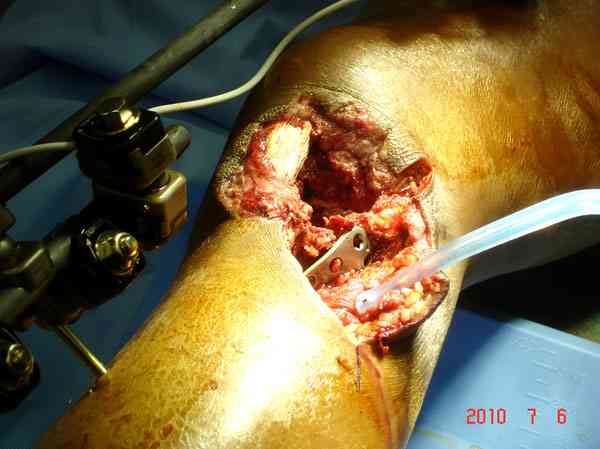

Тамошние доктора выполнили ПХО с удалением фрагментов латерального мыщелка бедра. Наложен АВФ. По возвращению в Украину через 1,5 месяца АВФ демонтирован. И так как смещение фрагментов бедра не устранено, было принято решение после заживление ран от стержней выполнить МОС. Не сколько для четкой анатомической репозиции сколько для подготовки к установке эндопротеза в будущем. Что и было выполнено 10 августа. Интраоперационная картина следующая. Дефицит практически всего латерального мыщелка бедра. Была выполнена попытка закрепить то что осталось от мыщелка, но он развалился на фрагменты. ВЫполнен ситуационный синтез спицами. Дефект заполнили бикортикальным трансплантатом из крыла подвздошной кости, МОС страйкеровским фиксатором. В послеоперационном периоде к 10 дню начались боли, гипертермия. Повышение СОЭ, лейкоцитоз. Посев крови транзиторная бактериемия золотистого стаф. Взяли в операционную. Выполнили дренирование сустава и области п\о раны. Получили гематому фактически с гноем. Температура нормализовалась. Назначили ванкомицин по 1000 мг 2 раза в день.который принимает с 28 августа по сей день. Температура нормальная, СОЭ на убыль. Посевы отделяемого стафилококк 2 ст активности. Но отделяемое по дренажам продолжает идти в достаточном количестве. Взял посев, сеется стаф. 3 ст активноси. К ванкомицину, понятно, слабочувствителен. Что в этой ситуации посоветуете?

Пожалуйста, снимки.

Коллеги фиксатор Numelock II

Здесь применение материала Plexur http://www.plexur.com для пластики при дефектах кости у больной с огнестрельной раной латерального тибиал плато с повреждением малоберцового нерва. Несмотря на интактный медиальный мышелок, для профилактики от вальгуса установлен АВФ и сделана ангиограмма.

После нескольких обработок и вакуумирования, поэтапно сделана фиксация тибиального бугра шурупами. И окончательную фиксацию закончили латеральной пластиной для тибиал плато и установкой пластического материала.